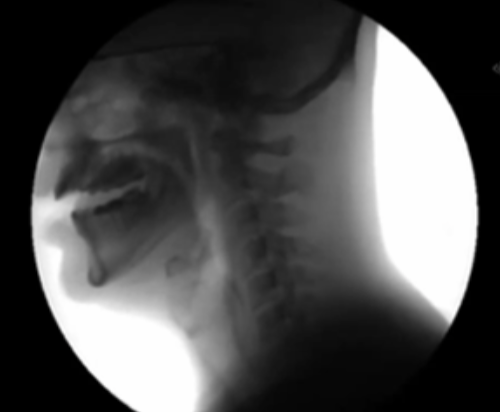

<p>What is happening in this picture?</p>

What is happening in this picture?

impaired swallowing (IX: the glossopharyngeal nerve)